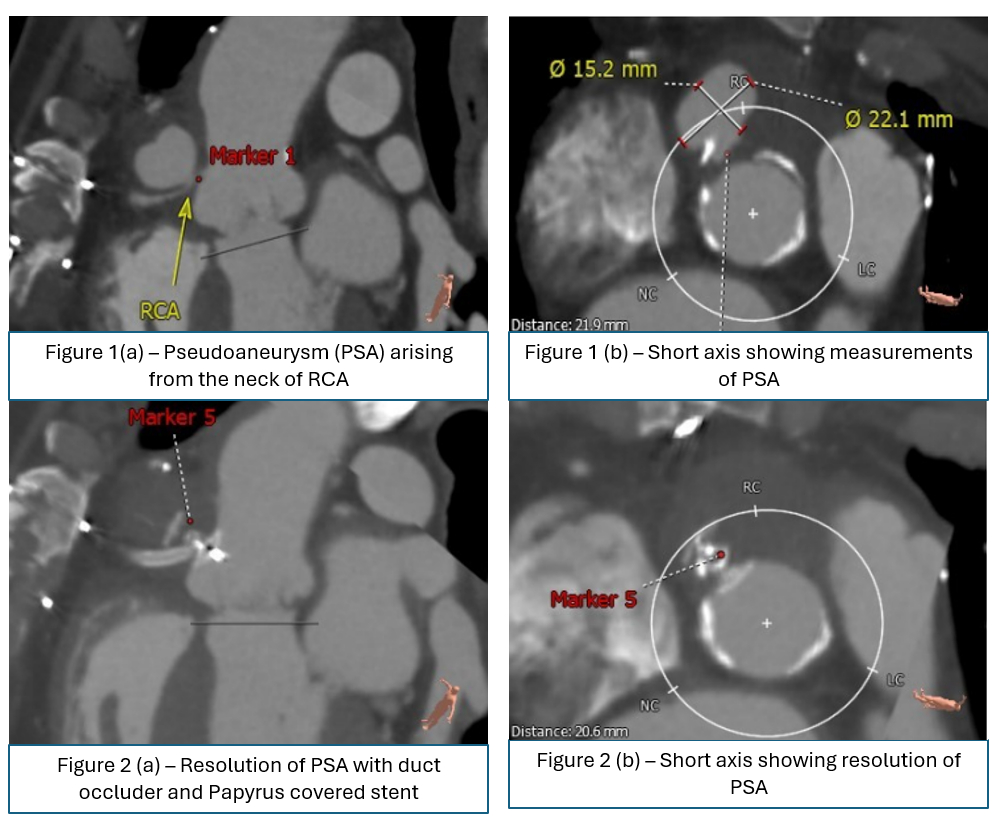

A man in his mid-70s with a complex cardiovascular history including coronary artery bypass grafting in 2020, treated aortic valve endocarditis in July 2024, and prior surgical patch repair of an aortic root PSA in September 2024, presented to the emergency department with 3 days of epigastric pain radiating to the back with nausea and mild dyspnea. Initial workup ruled out acute coronary syndrome, and CT angiography (CTA) revealed a focal type B aortic dissection and a persistent aortic root PSA measuring 1.5 x 2.2 cm, reduced from 3.0 x 4.6 cm before the patient’s previous surgery. Transesophageal echocardiography (TEE) showed an orifice adjacent to the right coronary cusp.

Given the high surgical risk, the multidisciplinary heart team recommended a transfemoral transcatheter approach. The PSA was successfully excluded using an Amplatzer Duct Occluder II device deployed across the neck of the aneurysm, and a Papyrus-covered stent was deployed in the RCA, ensuring complete sealing. The patient had been preloaded with dual antiplatelet therapy (DAPT).

The procedure was completed without complication, and the patient remained hemodynamically stable post-operatively. He was discharged on maintenance DAPT, and his post-procedure CT scan after 2 weeks showed exclusion of PSA.

Management of aortic PSAs is a challenging scenario with high mortality rates with sole medical therapy. Therefore, surgical intervention remains the mainstay of therapy. However, in the setting of high surgical risk, transcatheter approaches have emerged as a viable alternative option. In our case, a novel dual device transcatheter closure technique using a duct occluder, complemented by a covered stent, proved effective in allowing safe exclusion of the PSA while preserving right coronary flow.